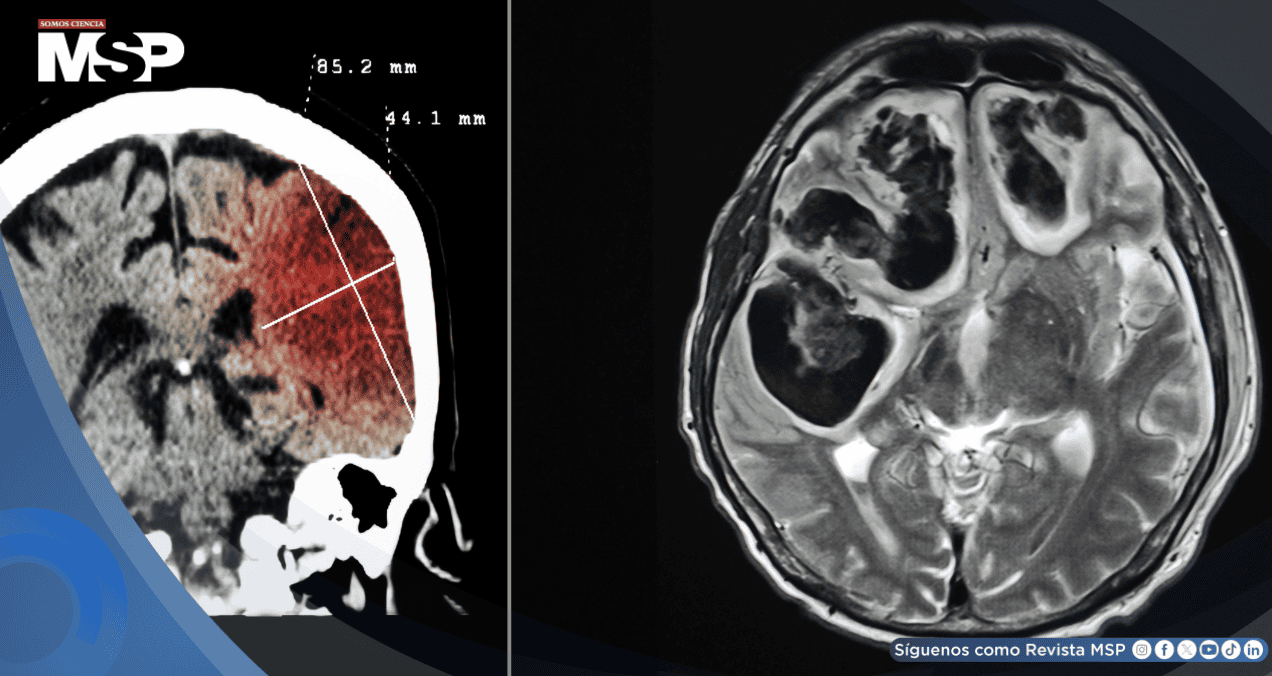

La sangre extravasada forma un hematoma que comprime el tejido cerebral circundante y eleva la presión intracraneana. Esto puede generar desplazamiento cerebral, herniación, coma y muerte. Si la sangre se filtra hacia los ventrículos, puede aparecer hidrocefalia aguda, lo que empeora el pronóstico.

La tomografía computarizada (TC) es el estudio de elección para detectar sangrados. Se complementa con pruebas de coagulación, hemograma y control de glucosa. Si la TC inicial es negativa, pero se sospecha una hemorragia subaracnoidea, se puede realizar una punción lumbar.

Evacuación quirúrgica en hematomas cerebelosos > 3 cm o hematomas lobares que causan desplazamiento.